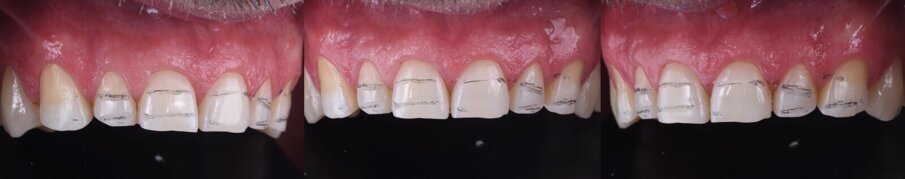

Následně byl zhotoven digitální wax-up ve frontálním úseku horní čelisti, aby bylo možno ověřit estetiku plánované rekonstrukce a vést minimálně invazivní preparaci zubů na základě zhotoveného mock-upu (obr. 8). Finální preparace (obr. 9) se z větší části omezila na interproximální oblasti (obr. 10). Poté byl proveden finální digitální otisk při aplikaci retrakční niti. (obr. 11).

Obr. 8a, b: Anteriorní wax-up.

Obr. 8c–e: Anteriorní mock-up.

Obr. 9a–f: Vodicí drážky pro preparaci.